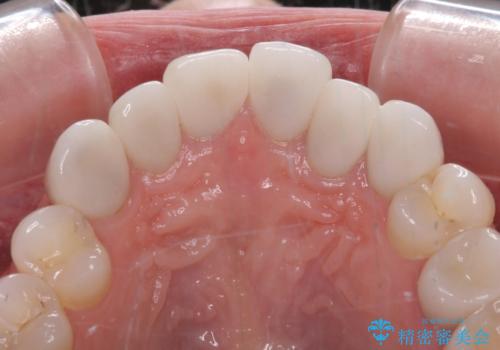

矯正治療自体はインビザラインで満足のいく仕上がりとなりました。

欠損部位は傾斜歯軸を起き上がらせることができたため、オールセラミッククブリッジにて補綴治療を行いました。

全顎的に満足のいく仕上がりとなりました。